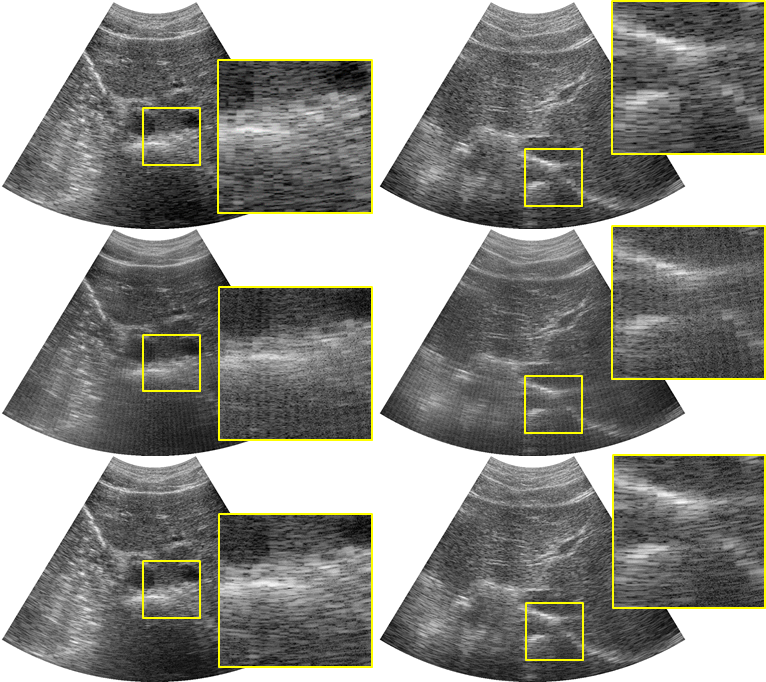

Refer to caption

Fig. 5: Convex transducer US images from (first row) full RF data, (second row) x4 downsampled RF data, and (last row) proposed CNN-based interpolation from x4 sub-sampled RF data.

Next, we use the network trained using the RF data from linear array transducer to interpolate the missing RF data from a convex array probe. The reconstruction results from a DAS beamformer are shown in in Fig.5. Because the Rx-SC data of linear array transducer and convex array transducer are similar, the DAS beamformer provided very accurate reconstruction results without any line artifacts or blurring from CNN-based RF interpolation. It is also remarkable that the accurate reconstruction was obtained for the liver region, which was never seen by the network trained using the linear array transducer data. The results confirmed the universality of the algorithm.